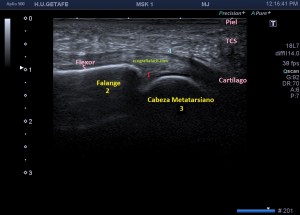

Cuando realizamos el estudio de la planta del pie en busca de patología a nivel metatarsal, como por ejemplo, el Neuroma de Morton, debemos descartar otras patologías que pueden cursar con un dolor similar al provocado por el tumor del nervio, bursitis, tenosinovitis de los flexores de los metatarsianos pueden ser alguna de ellas.

Para mi entender la anatomía me resultó vital, para luego poder correlacionar con la ecoarquitectura…en la imagen 1 puedes ver un dibujo, lo siento, no soy Monet como muy bien puedes comprobar, pero espero que te sirva para que entiendas como es la anatomía, superbásica, de un corte sagital de una metatarsiano en la articulación de la cabeza del metatarsiano (3) con la falange proximal (2) y su relación con la placa plantar (1), en rojo, el tendón flexor del dedo que estemos estudiando (5), en rosa, y la vaina que lo rodea (4), en azul…imposible olvidarme del verde, es la fascia plantar y es el número 6.

Aprendí que para estudiar una lesión debes conocer la mecánica de la lesión, en este caso, es una hiper extensión de la articulación que hace que la placa plantar estire demasiado y se pueda llegar a romper, lo que puede provocar líquido en la zona. Es una típica lesión de bailarinas, deportistas en general y personas que usan tacones muy pronunciados en sus zapatos. Te dejo la imagen número 2, donde puedes ver el teórico foco de una lesión marcada con una estrellas de 5 puntas como la de mi escudo.

Anatómicamente la placa plantar es una estructura fibrocartilaginosa altamente resistente debido al colágeno tipo 1. Ecográficamente, está entre el flexor del dedo y la cabeza del metatarsiano y su aspecto es hiperecogénico, ocupando el espacio que va desde el cuello del metatarsiano hasta la porción distal y plantar de la falange articular con el metatarsiano. Imagen 3 y 4, normalidad ecográfica. Imagen 5, imagen patológica.

Si sabemos que la estructura es de una intensidad ecogénica alta, la aparición de focos hipoecogénicos en el lugar pueden ser constitutivos de lesión locoregional, temerosos siempre de la anisotropía, aunque no es una anatomía tendinosa, la colocación de la sonda no es fácil por la orografía de la zona y por tanto, siempre con las orejas de punta…y gel, usamos mucho gel para que el apoyo sea perfecto. Te he dicho anteriormente que la rotura de esta estructura puede acarrear a presencia de líquido que se verá anecoico en la zona.

Estudiamos y demostramos la lesión o la normalidad en dos proyecciones, imagen 6, eje largo y eje corto de la zona y podemos comparar siempre con el lado contralateral, previsiblemente sano, dicho todo este conglomerado de ideas…las imágenes:

Marcadas con flecha azul puedes ver un efecto de discontinuidad a nivel de la placa plantar, hipoecogénico e irregular, demostrado en dos proyecciones.